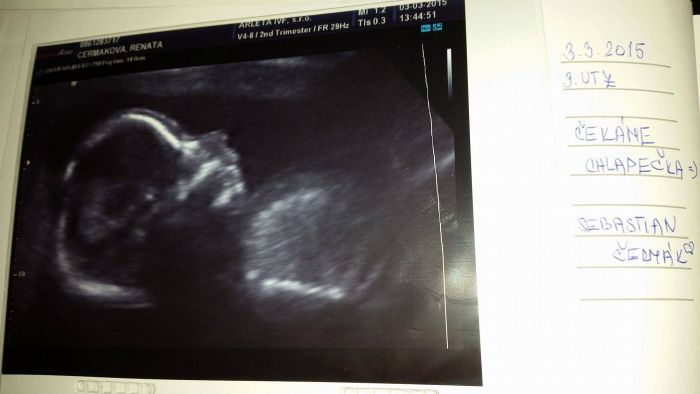

Ahojda holky, tak se musím pochlubit

Dnes byl se mnou poprvé manžel na UTZ a dozvěděli jsme se, že čekáme chlapečka

, kterého jsme hrozně chtěli... Tak mám dnes ohromnou radost. Prcek je zdravý a velebí si v bříšku

[710379] Leni ano už máme, Sebastian Čermák

Jméno už máme z minulého roku.... to jsem bohlužel potratila... ale tohle jméno pro klučinu nás drží stále

Jéé tak ať jste všichni v pořádku :-) Krásná fotečka, taky jsem chtěla foto, když jsme byli v 16tt na UZ a to naše mrně bylo zádičkama... nebylo co tisknout, tak doufám, že v pondělí bude líp natočené :-) A že se dr pokusí udělat foto, páč minule říkal, že by to stejně bylo rozmazané... nebo má nějakej starej UZ a nechce to říct. Taky by mě zajímalo co se zkoumá při 2.screeningu, jdeme na něj 25.3. :-)